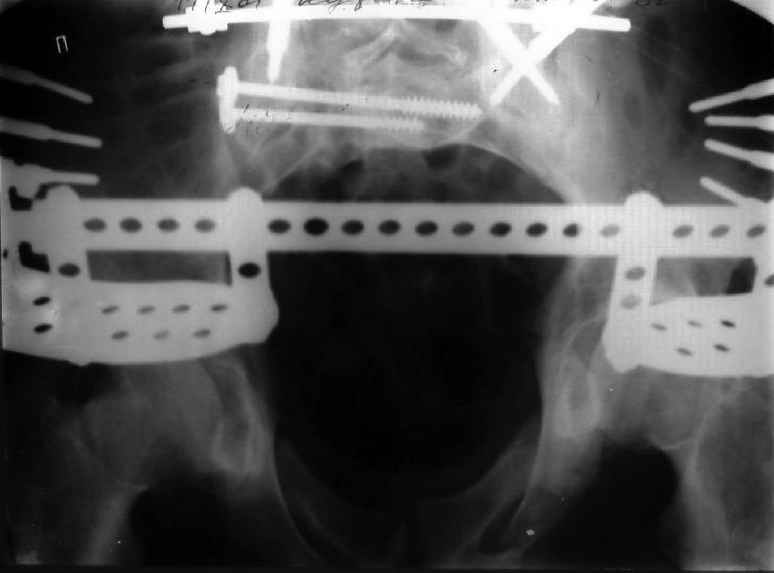

Уважаемые коллеги! Хотел-бы обсудить варианты лечения больной с застарелым переломом таза. Возраст 40 лет. Травма 11 месяцев назад. Главный травматолог Камчатского Военно-морского госпиталя Юрий Алексеевич Булахтин

У больного судя по всему вертикальная деформация таза. А каковы основные жалобы пациента и какие у него функциональные требования?

Мы, как правило, в подобных случаях проводим оперативное лечение в несколько этапов. Первым устраняем деформацию при помощи АВФ (кольцевой конструкции с фиксацией задних отделов), вторым- выполняем введение илиосакралых винтов, накостный остеосинтез передних отделов.

Для информации к размышлению о возможности исправления имеющейся деформации предлагаю похожий случай.